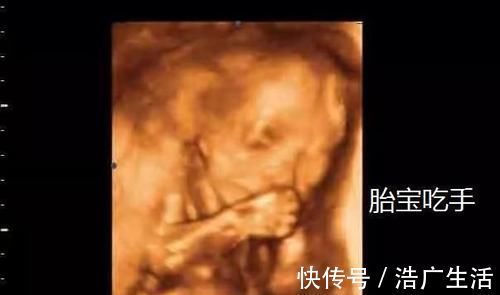

文章插图

胎儿虽然在肚子里吃不到食物,但是他在16周的时候就已经开始慢慢得学会吞羊水了,我们在做四维B超的时候,可能会大多数宝妈发现自己的孩子在宝妈肚子里允吸手指,而这也正是他们新学的一种生活小乐趣,甚至会在肚子里进行踢脚,自娱自乐。